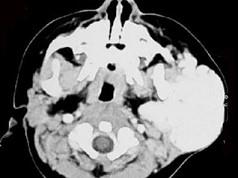

问题 1岁女孩,左耳垂下进行性增大肿块3个月,触之质软,下面是其颈部CT检查结果,其中左图是普通扫描,右图是增强扫描。请问,患者最可能的诊断是 ( )

选项 A、腮腺淋巴结结核 B、腮腺黏液表皮样癌 C、腮腺腺样囊性癌 D、腮腺血管瘤 E、腮腺混合瘤

答案 D